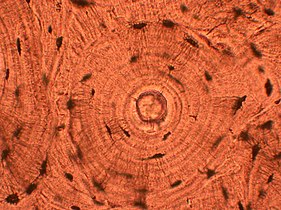

Whorled: Multiple concentric objects, or spiral-shaped

Cartwheel pattern: Center points that radiate cells or connective tissue outward